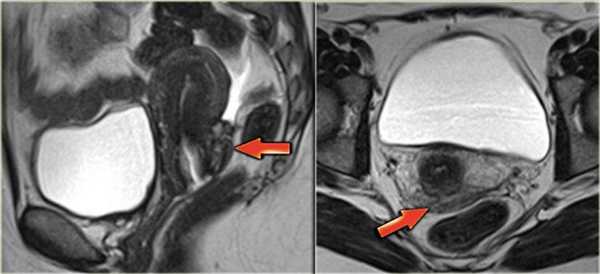

КТ- и МР-признаки эндометриоза брюшной стенки не являются специфичными: и при КТ, и при МРТ обнаруживается солидное образование в брюшной стенке, накапливающее контраст.

Эндометриоз передней брюшной стенки: фото МРТ. Очаг поражения обладает интенсивностью сигнала, сравнимой с мышцами, содержит также мелкие гиперинтенсивные очажки, отображающие расширенные эндометриальные железы. Они характеризуются слегка более интенсивным сигналом по сравнению с мышцами на Т1 ВИ с жироподавлением (стрелка)

На аксиальной Т2 ВИ МР-томограмме продемонстрирован другой пример поражения брюшной стенки.